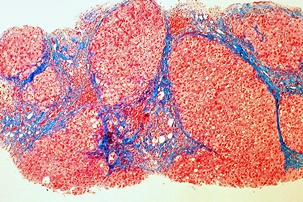

몸에 필요한 황색의 담즙색소 (빌리루빈)이 과도하게 쌓여 눈동자나 피부 등에 착색되는 현상을 말한다고 합니다. 이 담즙색소는 체내에 들어온 물질들이 분해되는 과정에서 생성되는 필요 없는 물질인데요. 일반적으로는 간에서 해독작용을 거친 후에 담즙으로 배설이 되는 것이 정상적이지만, 그렇지 못한 경우 황달이 발생하게 된다고 합니다.

황달이 생기는 이유는 담즙색소라고 알려진 빌리루빈이 과도하게 생기기 때문입니다. 빌리루빈은 우리 몸의 오래된 적혈구가 파괴되면서 생기는 물질인데요. 이 물질은 담즙에 녹아서 우리 몸의 배설물과 함께 배출이 되는 것이 정상적이지만 빌리루빈의 과잉생산이나, 간의 장애, 간세포나 담도의 손상에 의해 빌리루빈이 역류할 경우 발생된다고 합니다.